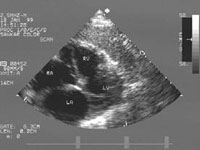

APICAL FOUR CHAMPER VIEW

Apical 4 chamber view

Structure from apex to base:

·Pericardium all around

·Apex at Top

·IVS ® central cardiac body ® IAS (Dividing the view into left 3/5 or 2/3 and Right 2/5 or 1/3).

·Left 3/5 or 2/3: LV(Lateral wall & cavity), MV(Leaflets & opening), ® LA(cavity & wall with openings of pulm. veins).

·Rt 2/5 or 1/3: RV(Lat wall & cavity), TV(Ant & Sept. leflets & opening) ® RA (cavity & wall).